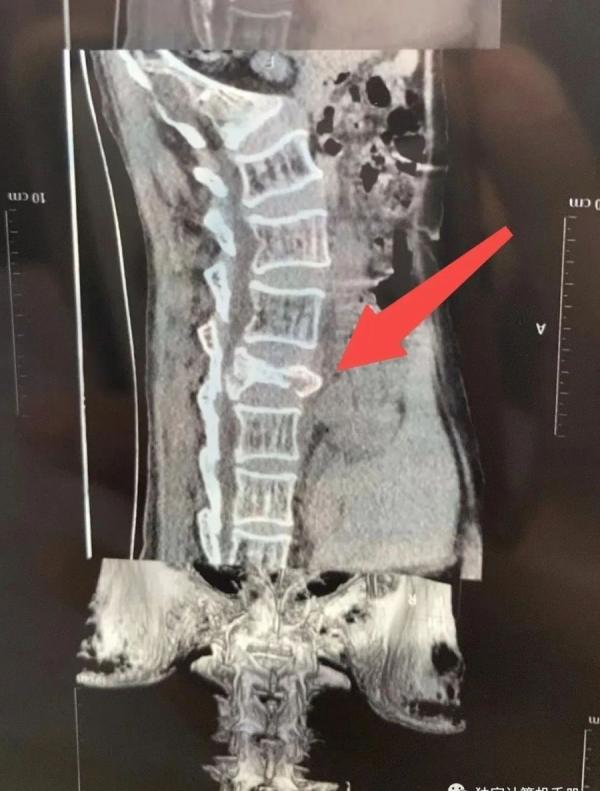

邓召美腰椎三处骨折。 (图片来源:网络截图)

腰椎3处骨折、爆裂性骨折,报警却不受理

她被带到镇政府的车送往县里医院后检查身体。2023.9.2凌晨出报告是:腰椎三处骨折,爆裂性骨折,需要住院。医务人员说,可能构成轻伤了,得去做鉴定。她的胳膊上有大片淤青。